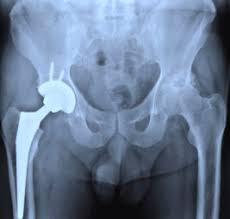

पैर और कूल्हे (Glutes) मानव शरीर की नींव हैं। यहाँ की कमजोरी अक्सर संतुलन की समस्या और पीठ दर्द का कारण बनती है।